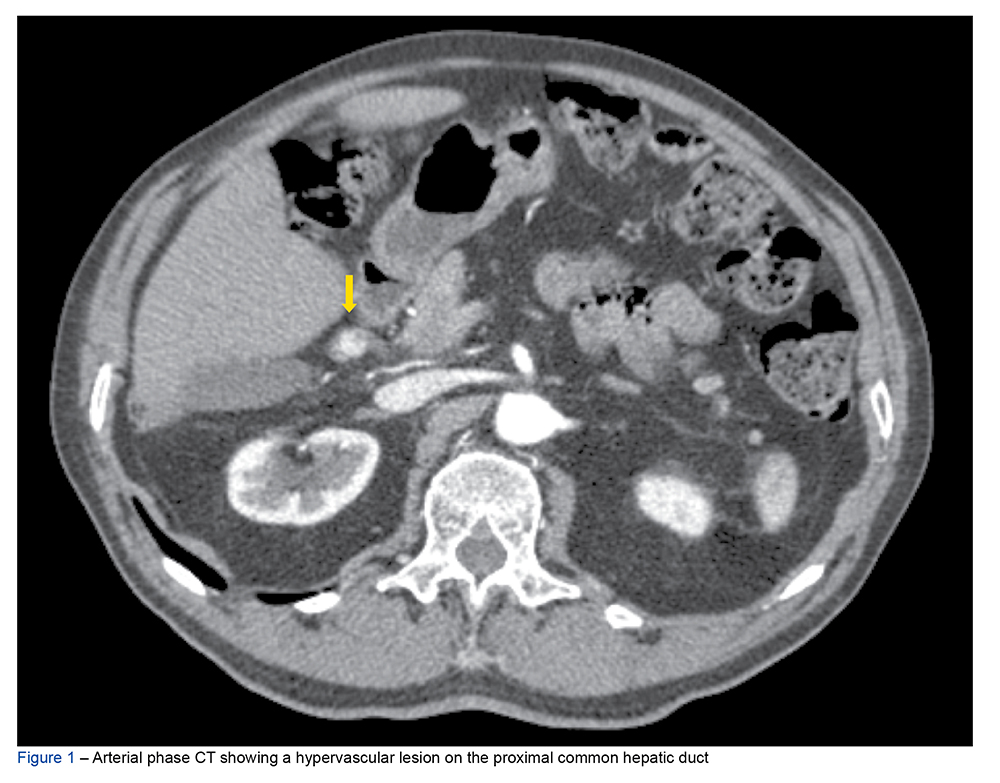

Neurofibromatosis type 1 (NFT1) is a disease caused by mutations in the tumor suppressor gene NF1. It is associated with a higher incidence of chromaffin cell tumors w...